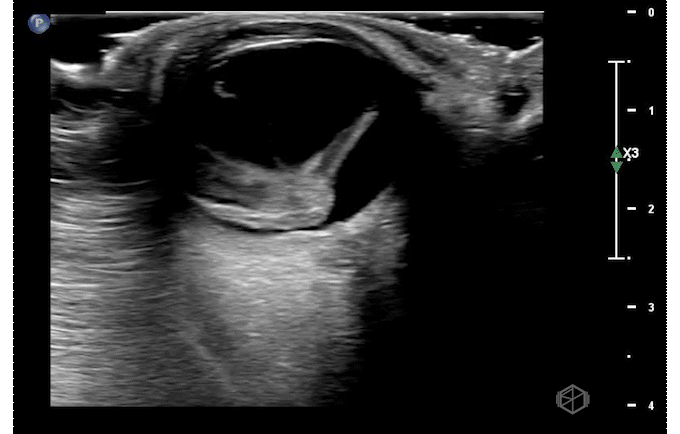

Dr. Singh had an 80-year-old female present for right eye vision loss. The patient was called a stroke alert. However, Dr. Singh was not entirely convinced it was a stroke and went one step further — he did a POCUS of the patient’s right eye and saw the below findings:

This patient has heterogeneous echogenic material within the vitreous body. There is no obvious thick membrane visible attached to the optic nerve making retinal detachment unlikely.

Diagnosis — Right eye vitreous hemorrhage

• Vitreous hemorrhage can be due to abnormal vessels (eg, diabetes, sickle cell, retinal vein occlusion etc.), rupture of normal vessels (trauma, vitreous detachment, coagulopathy, Terson’ syndrome — SAH causing increased ICP etc.), or blood from an adjacent source.

• The vitreous humor is an avascular gel-like substance that is between the lens and the retina made up of ~99% water and ~1% collagen and hyaluronic acid; vitreous hemorrhage occurs when extravasated blood enters the vitreous humor of the eye (9265701).

• Appearance can depend on age of the hemorrhage — fresh hemorrhage can be wispy and mobile mildly echogenic opacities in the vitreous body. May appear more “washing machine like.” At this stage it is very important to evaluate with higher gain and perform oculo-kinetics to see the subtle hemorrhage or if a membrane present as well.

• It is very important to evaluate for retinal detachment as this increases the urgency for treatment.

• As the hemorrhage becomes older, it is possible to see organized echogenic opacities that layer with gravity (as seen in this example) (30977855).